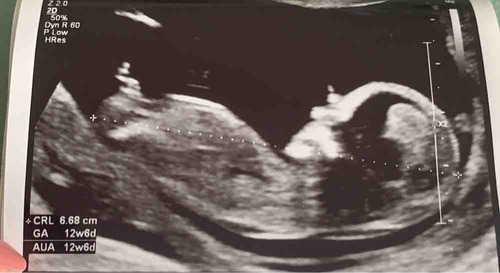

Ik had in deel 25 al een foto geplaatst van mijn laatste echo (andere dan deze), ik was toen 12 weken zwanger. Nu had ik het idee dat deze foto misschien wat duidelijker was. Ik vraag me af wat wat is. Wat denken jullie?? 😁

Ik had in deel 25 al een foto geplaatst van mijn laatste echo (andere dan d ...

Meisje